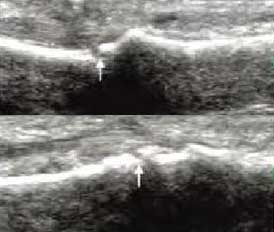

3、准确判断关节积液增加,精准判定RA严重程度

类风湿关节滑膜炎症会导致滑液渗出不断增多,形成关节腔积液。肌骨超声少可发现1ml的积液,能对关节腔积液量及位置准确定位,通过检测判定关节腔内液性边界清楚的无回声区、细点状回声或细微的低回声条纹,判断其宽度和深度衡量积液量的多少,进而评估RA的严重程度。

Ⅰ级微量积液

滑膜囊内见前后径3.55mm液性暗区,呈椭圆形

Ⅱ级较多量积液

暗区内有团状高回声,可见深度达6.46mm液性暗区

Ⅲ级大量积液

关节囊扩张,可见大范围液性暗区,髌上囊积液深度达11.2mm